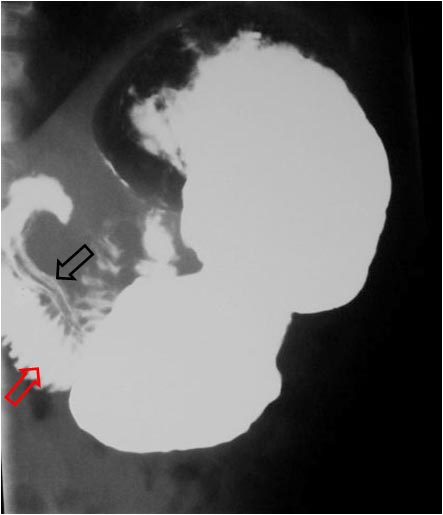

SIGNO DEL PSEUDOTUMOR DUODENAL

En la radiografía simple de abdomen, el bulbo duodenal lleno de líquido produce una imagen nodular o pseudotumoral, tal como vemos en la imagen (flecha). No debe confundirse con una litiasis biliar, que ocupa una posición similar pero que, cuando es visible, es porque tiene una densidad cálcica.

Este signo también se ha llamado Signo del pseudotumor del hipocondrio derecho.